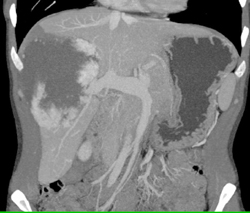

Hepatoblastoma